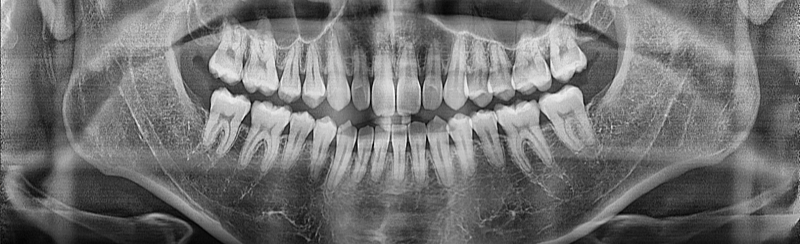

앞니 치아뿌리가 짧은지 알수있나요?

앞니 치아뿌리가 짧은건가요?

치과에서 교정 중 정출과정 있을 수 있다고 말씀하셨는데 치아지지에 문제가 없을까요 치과쌤은 약간만 와이어로 이동하는거라 문제없을거라고 하셨었습니다

일반인에 비해서는 앞니의 뿌리가 긴편은 아니나 정상적인 수준이며 병적인 상태가 아닙니다. 해당 사진으로 보았을 때 교정적으로 1~2mm 이동하더라도 전혀 문제가 되지 않으며 1~2mm 이동은 많이 이동하는 것이 아닙니다. 교정 와이어로 쉽게 이동이 가능할 것으로 보입니다.

앞니 치아 뿌리가 약간 짧지만 교정하신다고 크게문제가 되지는 않을것같습니다. 교정을 하시게 되면 양치가 어려우니 치아관리를 정말 잘하셔야됩니다.

사진으로만 봤을 경우에는 전치부위의 뿌리길이는 정상으로 보입니다.

교정을 하는 도중에 치아 뿌리의 흡수나 정출현상이 발생할수 있기 때문에 치아의 뿌리가 정상적이고 잇몸에 염증이 없을때 교정을 하게 됩니다.

상악 앞니의 치아뿌리의 길이는 정출시 보다는 치아 함입시 영향이 있을수 있습니다. 교정 진단한곳에서 더 자세한 설명부탁드리면 친절히 답변해주실거 같습니다.